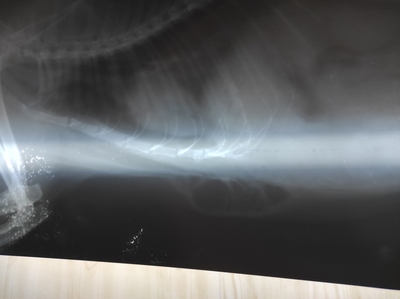

Только приехали от врачей. Помогал весь коллектив клиники. На рентгене видна гематома в месте удара, на животе синяк. Сломаны хрящи рëберные, немного воздуха под кожу вышло. Сделали тугую повязку, поставили уколы. Клетку для кроликов уже заказали, будет в ней жить ближайшее время. Состояние стабильное, прогнозы хорошие, а дальше видно будет.